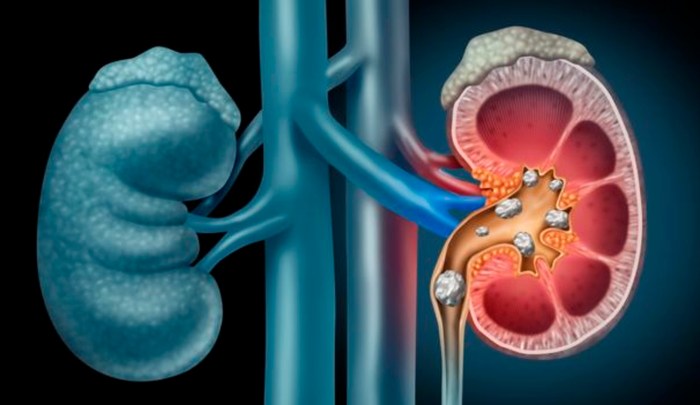

Cómo tratar los diferentes tipos de piedras de riñón o litiasis renal

La litiasis renal es una enfermedad muy frecuente con una elevada incidencia en la población general, con valores que van desde el 8-19% en varones y del 3-5% en mujeres, lo que comporta una elevada carga económica y clínica para el sistema de asistencia sanitaria. Otro factor de gran importancia es el elevado porcentaje de recidiva o … Continuar leyendo Cómo tratar los diferentes tipos de piedras de riñón o litiasis renal